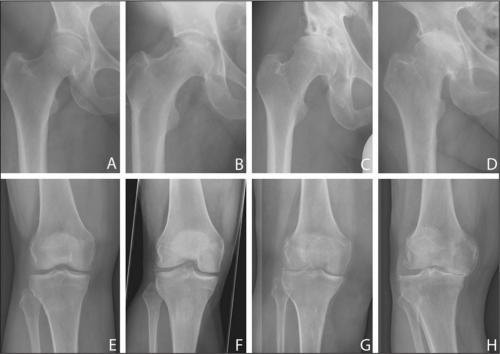

Дегенеративные изменения коленного и тазобедренного суставов.